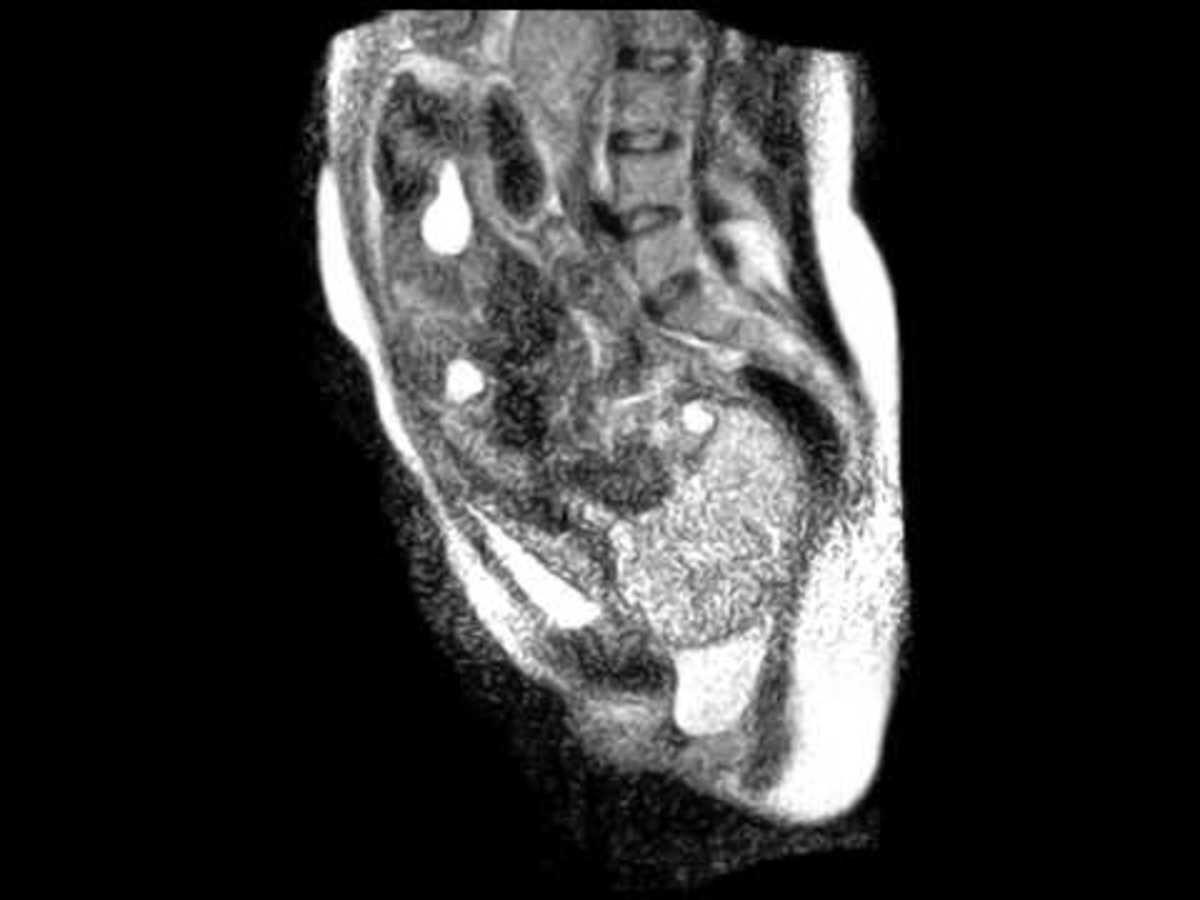

Το βίντεο που θα παρακολουθήσετε είναι εξαιρετικά σπάνιο. Σπάνιο από την άποψη ότι για πρώτη φορά στα χρονικά καταγράφεται μέσω μαγνητικού τομογράφου, η διαδικασία ενός τοκετού. Μια 24χρονη μανούλα δέχτηκε όταν ο γυναικολόγος της, της πρότεινε να πάρει μέρος σε κάτι που για πρώτη φορά στα χρονικά θα γινόταν. Θα καταγραφόταν ο τοκετός με έναν ειδικά τροποποιημένο μαγνητικό τομογράφο.

Όλα συνέβησαν σε μαιευτική κλινική του Βερολίνου. Ο γυναικολόγος της μανούλας Fridrich Guttler, συνέδεσε τον μαγνητικό τομογράφο και κατέγραψε τη γέννηση όπως ακριβώς θα την δείτε. Μπορείτε να διακρίνετε τις συσπάσεις της μήτρας αλλά και τη στιγμή που βγαίνει το μωρό. Οι γιατροί εκεί σταμάτησαν την καταγραφή προκειμένου το νεογέννητο να μην ακούσει τον θόρυβο του μαγνητικού.